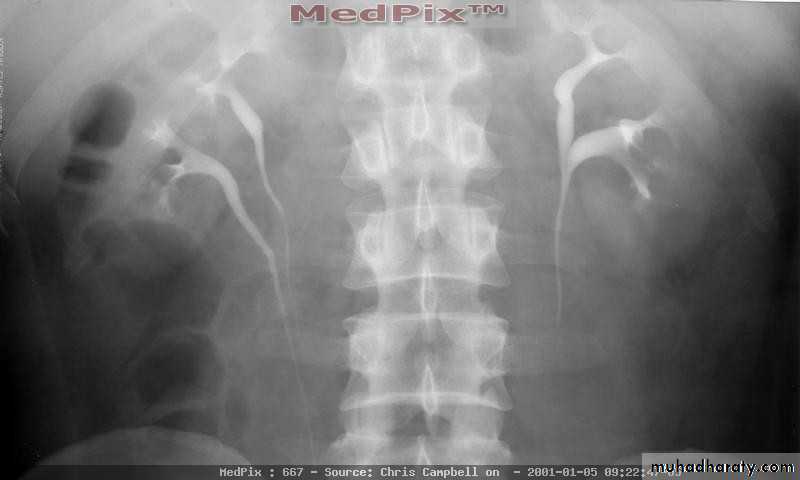

Horseshoe Kidney

found in 1:1000 necropsies an is commoner in men.

probably the most common of all renal fusion anomalies

The anomaly consists of two distinct renal masses lying

vertically on either side of the midline and connected at

their respective lower poles by a parenchymatous or fibrous

isthmus that crosses the midplane of the body.

Fusion of the renal masses early in embryonic life, so its ascent

will be impeded by inferior mesenteric artery.

The kidneys are low located, mal rotated and pelves lie anteriorly

Symptom When present, they are related to complications like hydronephrosis, infection, or calculus formation

Diagnosis ultrasound, IVU, CT scan